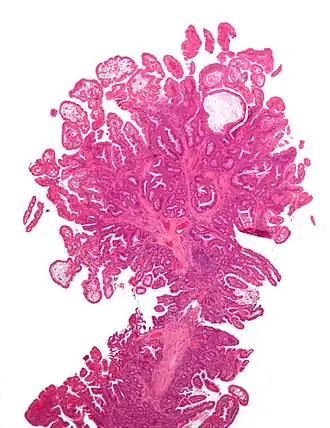

Le syndrome de Peutz-Jeghers (SPJ) est une maladie génétique rare caractérisée par le développement de polypes hamartomateux dans le tube digestif.

Les personnes atteintes de Peutz-Jeghers développent des polypes localisés au niveau de l’intestin grêle (70-90 %), du côlon (50 %) et de l’estomac (25 %)[1] principalement, qui ont une tendance à la cancérisation. Ces personnes ont donc un risque accru de cancers gastro-intestinaux, tel que le cancer du pancréas, de l'estomac, de l'intestin grêle et du colon, mais ont aussi un risque majoré de cancers extra-digestifs tel que le cancer du sein, du poumon, de l'utérus, des ovaires et des testicules. Ces polypes, à la base bénins, peuvent entrainer des complications tels qu’un saignement de ces polypes (responsables d’anémie ferriprive lorsqu’ils sont chroniques), une occlusion intestinale, un prolapsus rectal, une hémorragie digestive sévère avec anémie secondaire, et une invagination.

Comme mentionné, le Peutz-Jeghers possède des manifestations physiques externes (via les macules présentes sur les muqueuses) et internes (via les polypes hamartomateux et le risque accru de cancers invasifs dû à la délétion/mutation du gène suppresseur de tumeur).